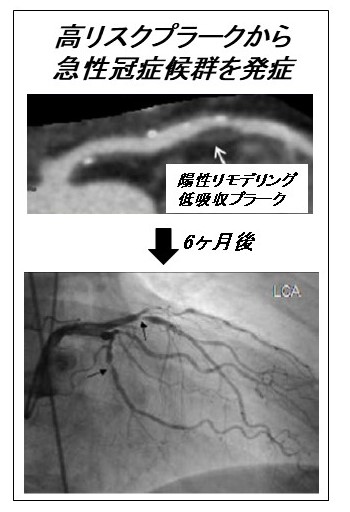

・冠動脈CTによる高リスクプラーク同定とバイオマーカーに関する研究

Motoyama S et al. JACC 2009 改変

冠動脈CTは、有意病変の有無だけでなくプラーク性状の評価が可能である。陽性リモデリングもしくは低吸収プラークの存在は、急性冠症候群を発症する可能性の高い“高リスクプラーク”とされている。我々は、血液検査による“高リスクプラーク”の検出について検討を行っている。簡便な血液検査で“高リスクプラーク”が同定できれば、積極的な治療介入が可能となるかもしれない。